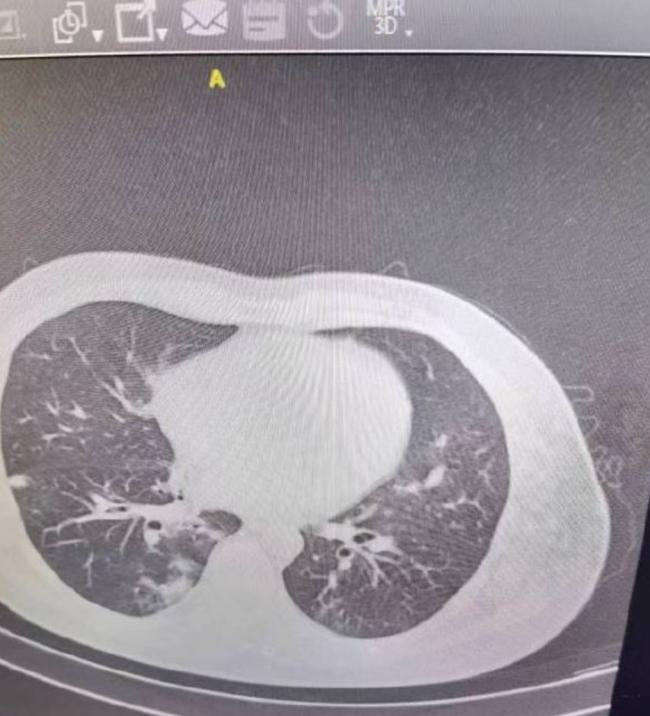

“争取几个月后我们就能扔掉口罩了。”内容表示,疫苗因种尽种,“肺结节问题,不听谣传,外科口罩一次性的,每次4小时要更换,我们很多人做不到。里面的纤维会被吸收进去,有这种可能,和疫苗没关系”,中国刚发布第4剂疫苗指南。“辉瑞的疫苗Paxlovid,对高危人群管用,对于年轻人没有效果”。